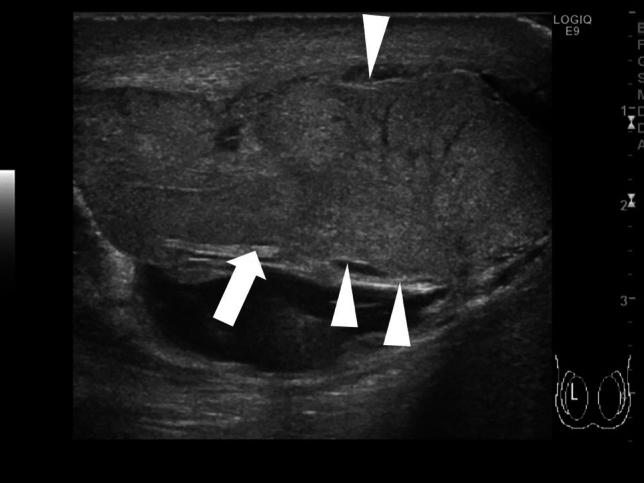

Testicular torsion is a urological emergency caused by the loss of testicular tissue due to ischemic damage. Rapid diagnosis and urgent treatment play a crucial role in the management of testicular torsion. Manual detorsion can be performed at the bedside, thereby reducing the duration of ischemia. Recent studies have reported the use of point-of-care ultrasonography for diagnosing testicular torsion; however, no review article has focused on the ultrasonographic findings pertaining to manual detorsion. This review describes the diagnosis of testicular torsion and the ultrasonographic indications for manual detorsion. Spermatic cord twisting or the whirlpool sign, absence of or decreased blood flow within the affected testis, abnormal testicular axis, abnormal echogenicity, and enlargement of the affected testis and epididymis due to ischemia are the sonographic findings associated with testicular torsion. The following findings are considered indications for manual detorsion: direction of testicular torsion, i.e., inner or outer direction (ultrasonographic accuracy of 70%), and the degree of spermatic cord twist. The following sonographic findings are used to determine whether the treatment was successful: presence of the whirlpool sign and the degree and extent of perfusion of the affected testis. Misdiagnosis of the direction of manual detorsion, a high degree of spermatic cord twisting and insufficient detorsion, testicular compartment syndrome, and testicular necrosis were found to result in treatment failure. The success of manual detorsion is determined based on the symptoms and sonographic findings. Subsequent surgical exploration is recommended in all cases, regardless of the success of manual detorsion.

睾丸扭转是一种泌尿外科急症,由缺血性损伤导致睾丸组织丧失引起。快速诊断和紧急治疗在睾丸扭转的管理中起着至关重要的作用。床边手动复位可减少缺血持续时间。最近的研究报告了使用即时超声检查来诊断睾丸扭转,但没有综述文章专门关注手动复位的超声表现。本文描述了睾丸扭转的诊断和手动复位的超声指征。精索扭曲或漩涡征、受累睾丸内无血流或血流减少、睾丸轴异常、回声异常以及缺血引起的受累睾丸和附睾增大是与睾丸扭转相关的超声表现。以下发现被认为是手动复位的指征:睾丸扭转的方向,即内旋或外旋(超声准确性为 70%)和精索扭转的程度。以下超声表现用于确定治疗是否成功:漩涡征的存在以及受累睾丸的灌注程度和范围。手动复位方向的误诊、精索扭转程度高和复位不足、睾丸间隔综合征和睾丸坏死均导致治疗失败。手动复位的成功与否取决于症状和超声表现。无论手动复位是否成功,都建议进行后续的手术探查。